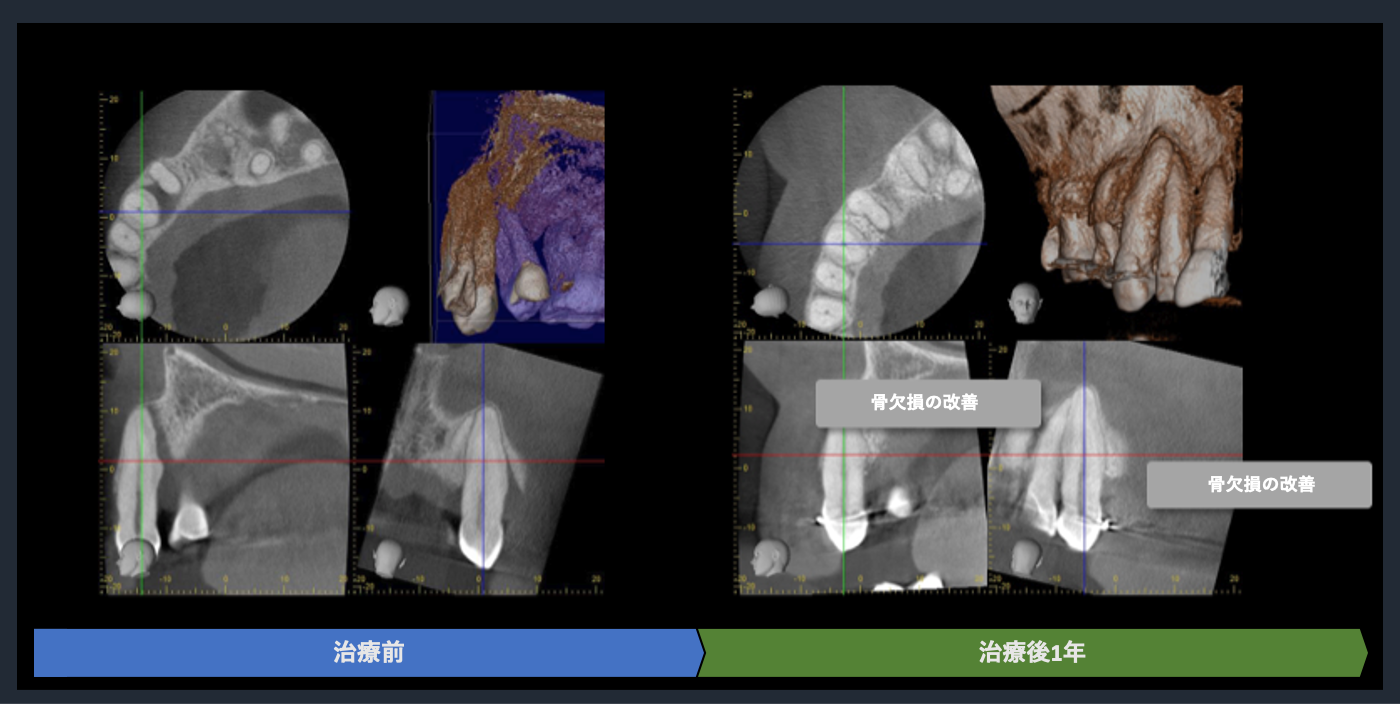

CTでの術前診査1

歯周基本治療後の再評価

Post-treatment evaluation

Post-treatment evaluation

CTでの術前診査2

| 概要 | 歯周病が進行しており、右上臼歯部に重度の骨吸収像が認められます。失われた骨を再生し、歯の生存率を高めることを目的に、再生療法を試みました。良好な結果を得ることができました。問題なく使っていただいております。 再生療法を行う利点としては、ポケットが浅くなるので、患者様ご自身でのブラッシングで管理し、コントロールすることが可能になります。もちろん定期的なメインテナンスは必要不可欠です。 |